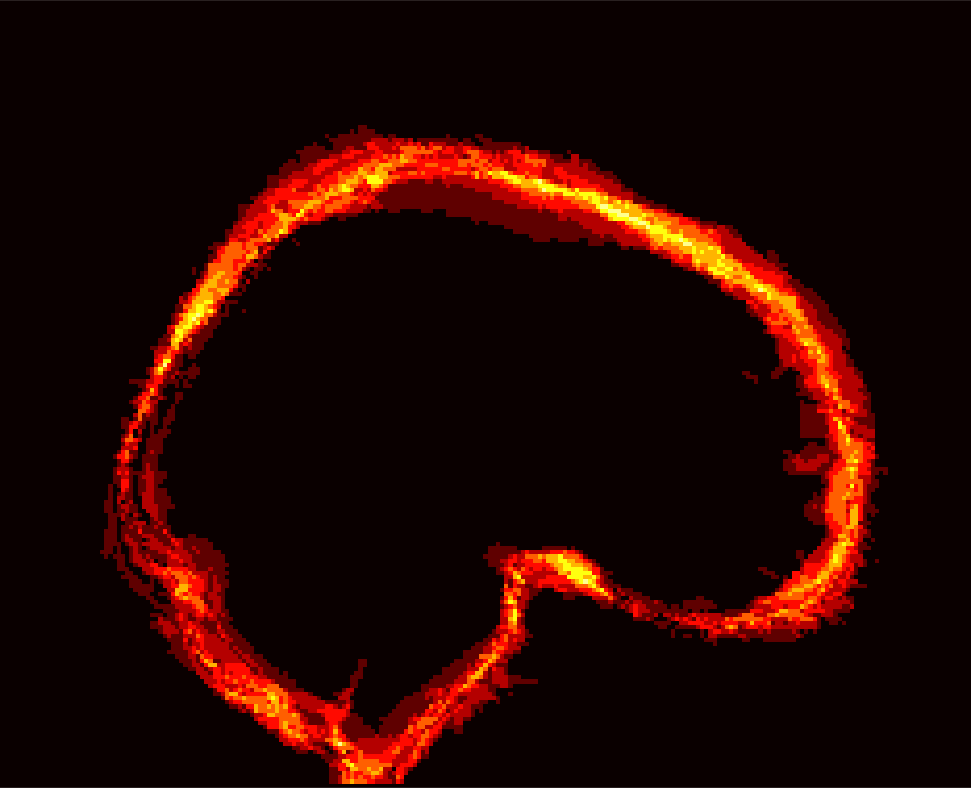

Figure 8: Example BRATS image with its decomposition result in atlas space. (a) Input image after pre-processing; (b) quasi-normal image L+M𝐿𝑀L+M; (c) non-brain image S𝑆S; (d) pathology image T𝑇T.

In addition to extracting the brain from pathological datasets, our method also allows for the estimation of a corresponding quasi-normal image in atlas space, although this is not the main goal of this paper. Fig.8 shows an example of the reconstructed quasi-normal image (L𝐿L) for an image of the BRATS dataset, as well as an estimation of the pathology (pathology image T𝑇T and non-brain image S𝑆S). Compared to the original image, the pathology shown in the quasi-normal image has been greatly reduced. Hence this image can be used for the registration with a normal image or a normal atlas. This has been shown to improve registration accuracy for the registration of pathological images [27]. Furthermore, an estimate of the pathology (here a tumor) is also obtained which may be useful for further analysis. Note that in this example image the total variation term captures more than just the tumor. This may be due to inconsistencies in the image appearance between the normal images (obtained from OASIS data) and the test dataset. As our goal is atlas alignment rather than quasi-normal image reconstruction or pathology segmentation, such a decomposition is acceptable, although we could improve this by tuning the parameters or applying regularization steps as in [27].